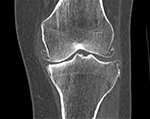

If you are a candidate for an ankle replacement, we will then obtain a CT (computed tomography) scan with multiple views creating a 3D assessment of your unique anatomy.

Your knee will be included in the CT scan to further improve alignment.

The CT scan allows us to create the patient-specific parameters used to plan and perform your surgical procedure with enhanced accuracy.